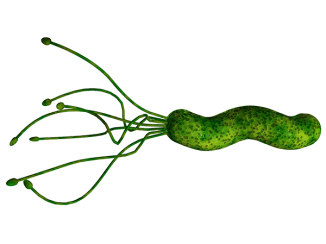

ამ ბაქტერიას წყლულის, ინფექციისა და კიბოს პროვოცირებაც კი შეუძლია! ებრძოლეთ მათ ამ საშუალებით...

ოდესმე გსმენიათ Helicobacter Pylori-ს (ჰელიკობაქტერ პილორი) შესახებ? ეს ბაქტერია მსოფლიოს მოსახლეობის 2/3-ის საჭმლის მომნელებელ ტრაქტში იმყოფება და..